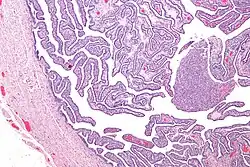

Definitive criteria include histopathologic evidence of endometritis, thickened, filled fallopian tubes, or laparoscopic findings. Gram stain/smear becomes definitive in the identification of rare, atypical and possibly more serious organisms.[24] Two-thirds of patients with laparoscopic evidence of previous PID were not aware they had PID, but even asymptomatic PID can cause serious harm.